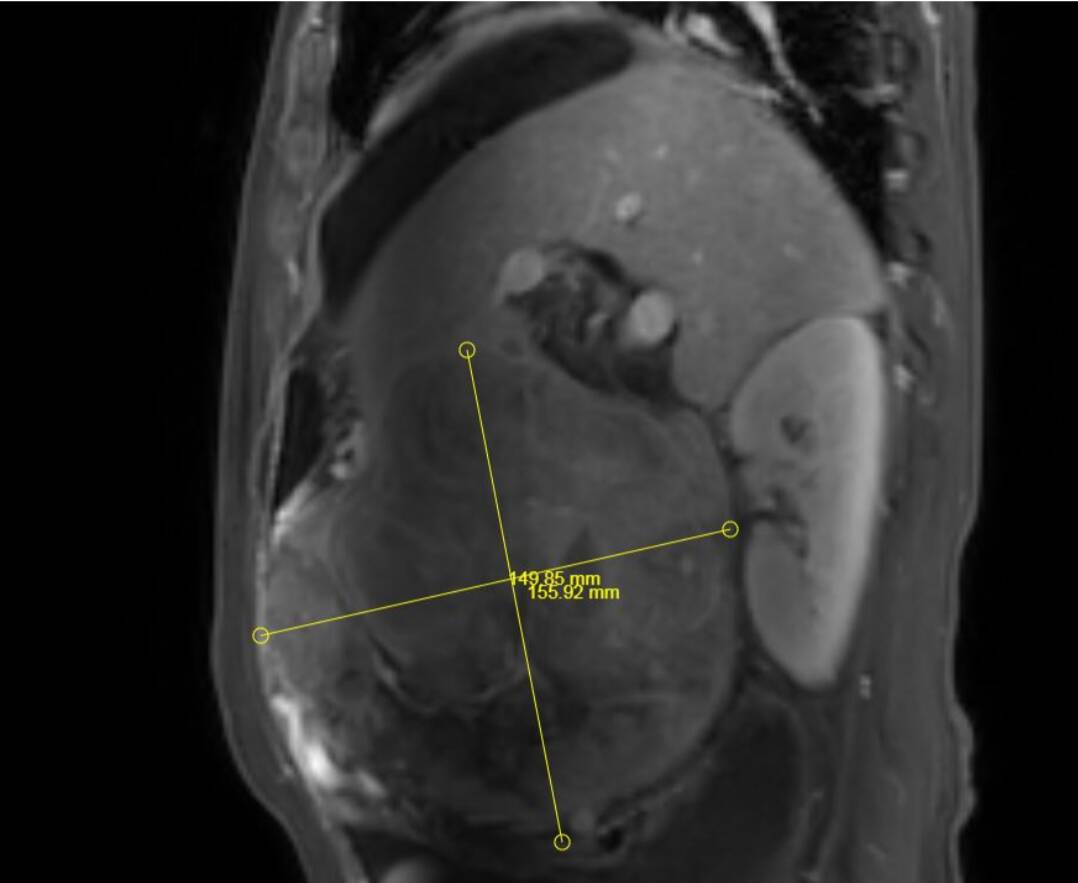

其中,成功为一名患者实施超大肝癌切除术,完整切除肿瘤大小达19cm×15cm,精准突破肝胆外科传统“手术禁区”,标志着普外二科在复杂肝胆肿瘤外科治疗领域迈上全新台阶。

此次切除的肿瘤体积巨大、血供丰富,与肝内重要血管、胆管粘连紧密,术中极易发生大出血、胆漏、肝功能衰竭等致命并发症。手术既要确保肿瘤完整根治、切缘干净,又要最大限度保留正常肝组织,难度与风险远超常规肝癌手术,对团队技术、经验与协作能力提出极高要求。

术前,科室联合影像、麻醉、重症监护、护理等多学科团队开展MDT会诊,全面评估肿瘤位置、大小、浸润范围及患者基础状况,精准规划切除路径与血管保护策略,反复推演手术流程,制定周密手术方案与应急预案,为手术成功筑牢坚实安全防线。